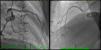

Coronary angiography revealed a 40% luminal stenosis in the left anterior descending artery (LAD) with no evidence of plaque rupture or thrombus (Figure 2A). Left ventriculography showed global hypokinesia with only mildly reduced left ventricular EF.

Despite her arterial hypotension, intravenous nitroglycerin was initiated with relief of chest pain, ST-T segment normalization and increase in blood pressure. Aspirin and bisoprolol were stopped and she was started on diltiazem 200 mg bid orally. After adequate informed consent had been obtained, pharmacological provocation testing for coronary artery spasm was performed with intracoronary injection of acetylcholine (ACh). After control coronary angiography, ACh was administered in a stepwise manner into the LAD (20–100 μg) and the right coronary artery (RCA) (20–50 μg) over a period of 20 seconds with a 3–5 min interval between injections. Coronary angiography was performed after each injection of ACh and when chest pain and/or ST changes were observed. At baseline coronary angiography showed no new stenosis or coronary blood flow impairment; after ACh injection into the LAD chest pain, ST-segment depression, LAD TIMI blood flow of 1 and transient grade 3 atrioventricular (AV) block were documented. Intracoronary administration of nitrates reversed the coronary spasm and AV conduction disturbances. Twenty minutes later, chest pain and ischemic ST changes recurred; response to nitrate infusion was poor and cardiac arrest with pulseless electrical activity occurred. Advanced life support was maintained for 32 minutes without return of spontaneous circulation.